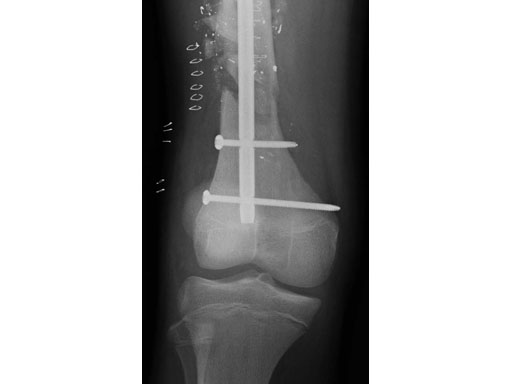

Fig 3ab AP x-rays 6 months postoperatively.